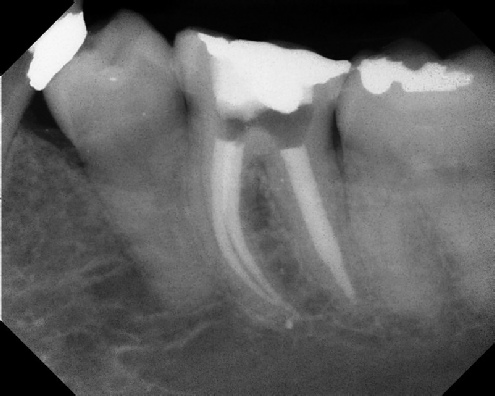

Root Canal Retreatment - Meriden 8 mos. recall Post-op Pre-op